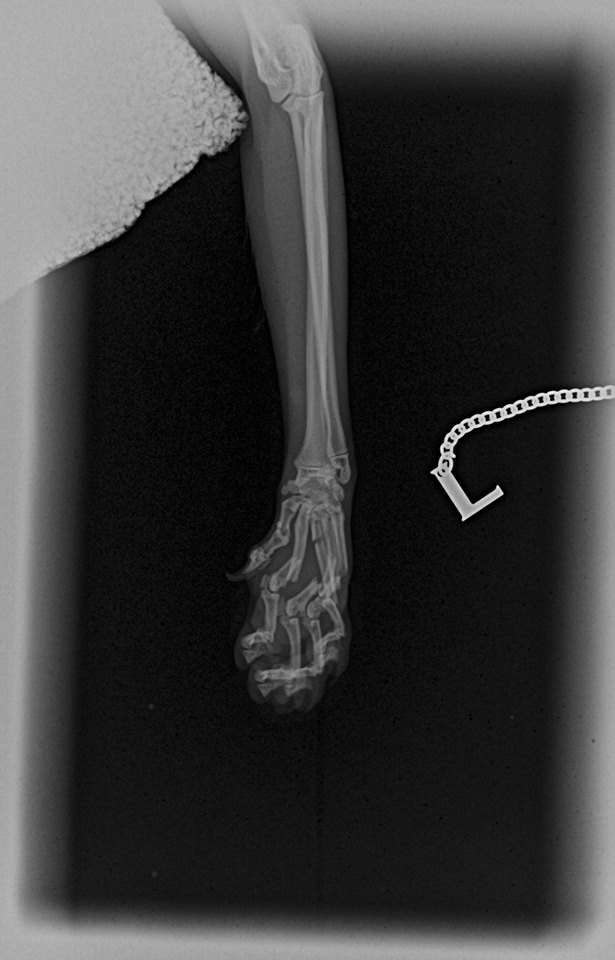

Tento černý kocourek spadl z 2. patra a zlomil si záprstí na jedné přední končetině. Konkrétně se jedná o sériovou frakturu všech metacarpálních kostí. Aby mohl zase běhat, bez operace se to neobešlo. Použili jsme externí skeletní fixaci tzv. „spider frame“, který poprvé použil Dr. Fitzpatrick, UK.